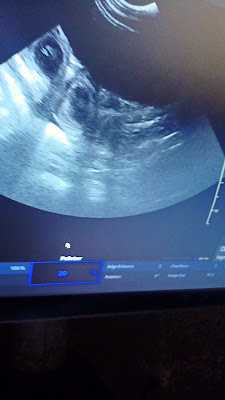

Tokio. 5 tydzień ciąży

Za nami kolejny tydzień ciąży Tokijki. Przyszła mama nadal jest bardzo wyciszona, dużo śpi, nadal jest nerwowa i ustawia wszystkich dookoła. Na szczęście apetyt nadal dopisuje A w brzuszku ...w brzuszku dzieją się cuda :)